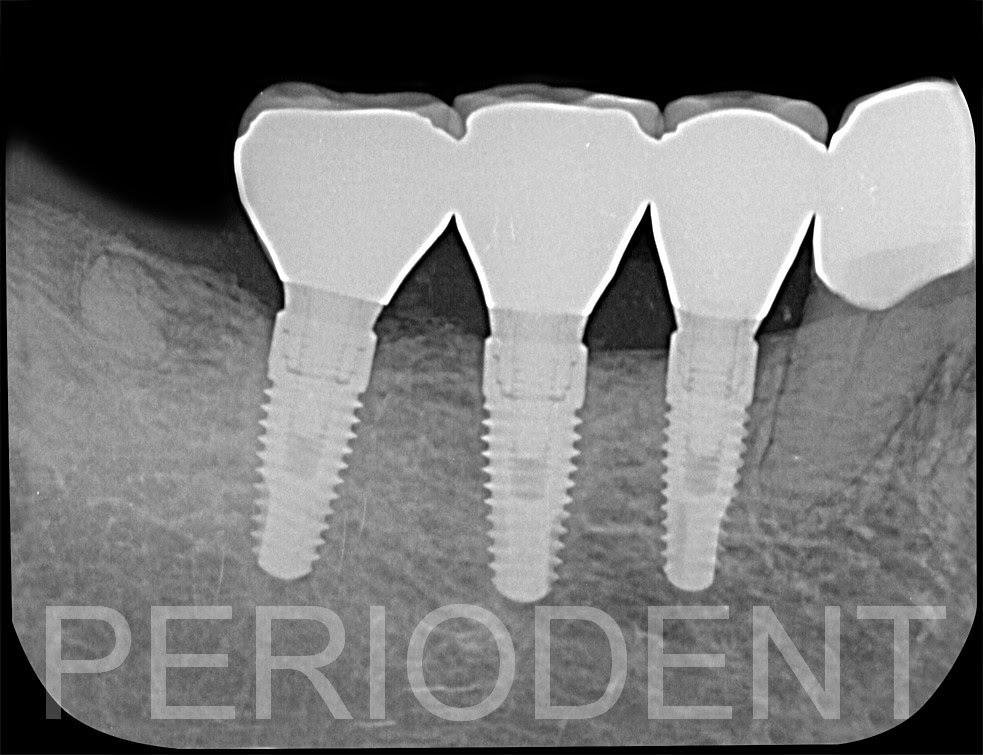

癒合後

取模裝上正式假牙